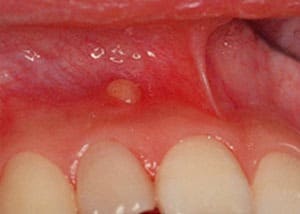

②歯周炎由来による歯周膿瘍

これに対して、歯の横に膿がたまる場合の多くは歯肉と歯周組織(歯周病)が原因で起こることがあります。